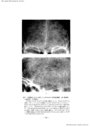

第3脳室近傍腫瘍の神経放射線診断-脳血管撮影を中心に- III 主に第3脳室の側方に発育する腫瘍(2)